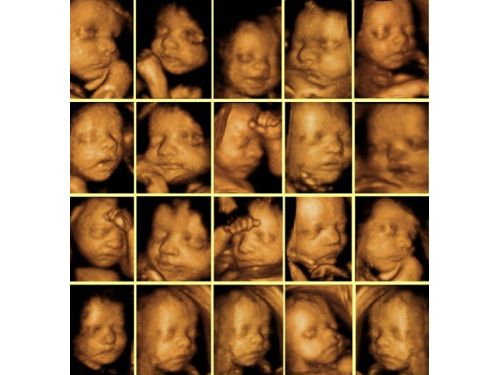

Ayrıca Opr. Dr. Ergun Özdemir Devlet Hastanesi Resmi web sitesinden yapılan açıklamada : Üçlü Tarama Testi:

Hastanemizin Yeni Doğan Ünitesinde artık üçlü tarama testi yapılmaktadır.Üçlü test tüm anne adaylarına 16.-18. gebelik haftaları arasında önerilen bir kan testidir. Anne adayından alınan kanda üç ayrı hormon ölçümü yapılır. Hormon ölçüm sonuçları, anne adayının yaşı, kilosu, . sigara kullanıp kullanmadığı gibi değişkenler ve gebelik haftasıyla birlikte özel bir bilgisayar programına girilerek işleme tabi tutulur. Bu işlem neticesinde anne adayının bebeğinde Trisomi 21 (Down sendromu), Trisomi 18 ve nöral tüp defekti (NTD) varolma olasılığıbelirlenir. Hazırlanan üçlü test raporunda bu üç anormal durum için risk ayrı ayrı belirtilir.